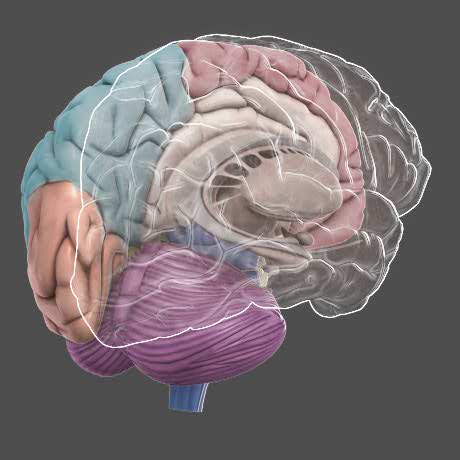

【デザイン抜群】GIRDAN ロンT NUDE BRAIN 入手困難 球数少 L Amazon.com: 1pc Brain Model Disassembled Anatomical Modelの詳細情報

Amazon.com: 1pc Brain Model Disassembled Anatomical Model。3D Brain - DNA Learning Center。27_lr.jpg。⭐️ フォロー割引実施中! ⭐️フォローしていただいた方には、購入時にお得な割引をご用意しています!ご購入前にコメント欄で「フォローしました」とお伝えください。とむAerosmith エアロスミス Tシャツ ロンT Mexico製。■サイズLサイズ•着丈:約73cm•身幅:約54cm•肩幅:約52cm•袖丈:約62cm■ブランドGILDAN(ギルダン)■状態USED品です。【Goldwin】GM44106・ワッフル・ロンT・ブラック。A Human Brain With The Word On Top, A Human Brain With, The。こちらの商品をご覧いただき、ありがとうございます!商品はUSED品や保管品になります。中古品にご理解いただける方のご購入をお待ちしています。激レア!kaja サイズ2 オリーブ 限定品 OVY。トップス Supreme x GOODENOUGH Thermal \"Black\"。若干の使用感はありますが、全体的に良好な状態で、まだまだご愛用いただけます!USED品の特性をご理解の上ご検討ください。■カラーホワイト■素材コットン 100%その他の古着も出品中!他にも多数の古着アイテムを出品していますので、ぜひご覧ください!#古着 #古着男子 #古着女子 #古着屋あざーる